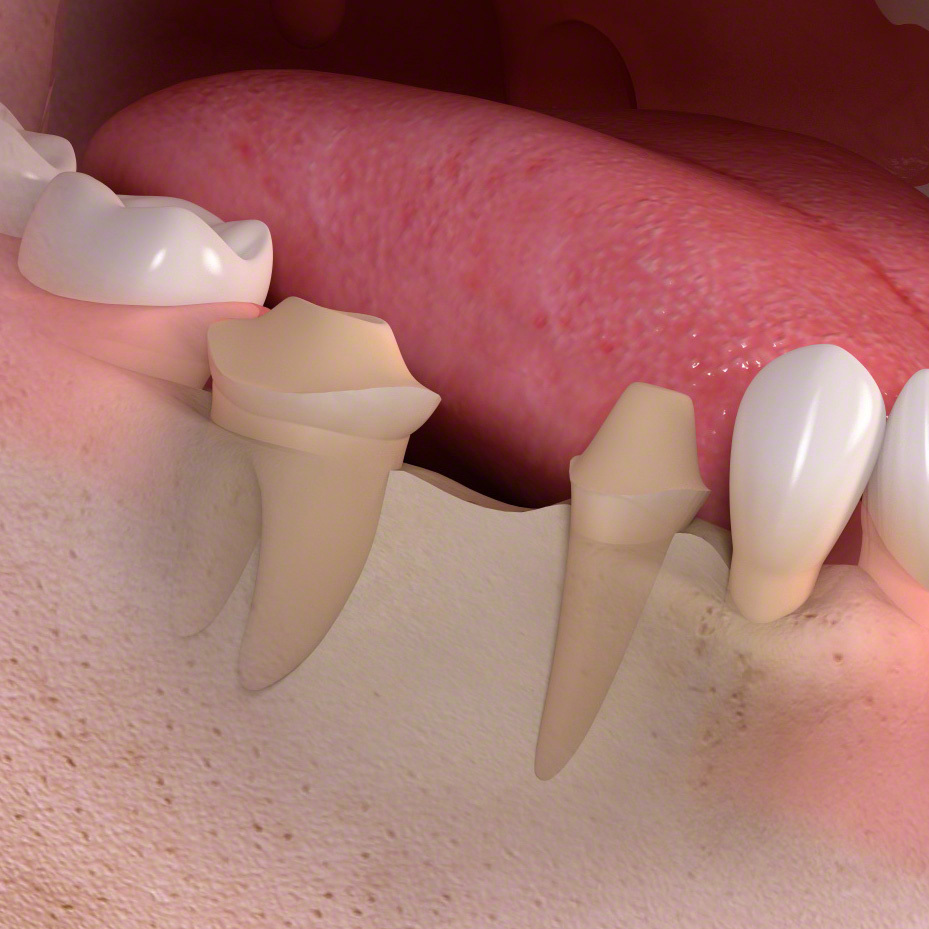

歯を失ったままにしておくと

• 1

歯根が失われると、骨に伝わる力がなくなり、歯を失った部分の骨がやせていきます。

• 2

歯の喪失によって歯が移動し、歯並びがかわってしまう場合があります。

• 3

歯の喪失によって、見た目が悪くなります。

• 4

骨の喪失によって顔の輪郭が変わってしまいます。